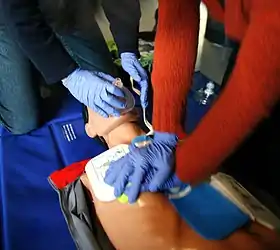

Defibrillators produce a defibrillation (electric shocks) that can restore the normal heart function of the victim.

Nevertheless, they are only indicated for some arrhythmias (abnormal heart beatings), specifically ventricular fibrillation (VF) and pulseless ventricular tachycardia. Defibrillation is not indicated if the patient is conscious or has a normal pulse. Defibrillation is also not indicated if the heart has completely stopped, as in asystole or pulseless electrical activity (PEA), in those cases a normal CPR would be used to oxygenate the brain until the heart function can be restored. Improperly given electrical shocks can cause dangerous arrhythmias, such as the ventricular fibrillation (VF).[45]

The standard defibrillation device, prepared for a fast use out of the medical centres, is the automated external defibrillator (AED), a portable machine of small size (similar to a briefcase) that can be used by any user with no previous training. That machine produces recorded voice instructions that guide to the user along the defibrillation process. It also checks the victim's condition to apply automatically electric shocks at a correct level, if they are needed. Other models are semi-automatic and need that the user push a button before producing an electric shock.

The defibrillation process is simple, but there exist written instructions of defibrillators that explain it step-by-step.